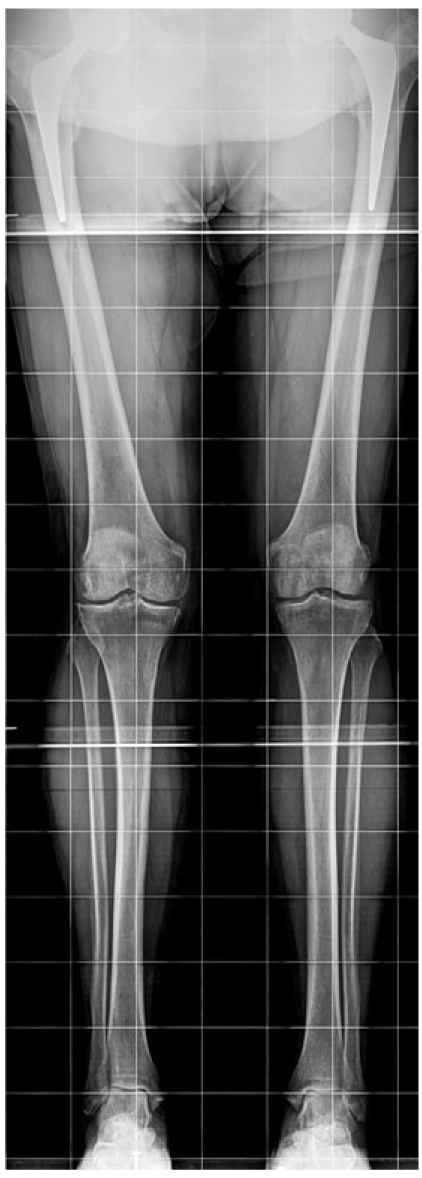

- телерентгенография (панорамный снимок) обеих нижних конечностей (рис. 4).

Рис. 4. Телерентгенограмма пациента с латеральным гонартрозом перед выполнением парциальной артропластики

Fig. 4. Full-length X-ray of a patient with lateral knee osteoarthritis prior to partial arthroplasty